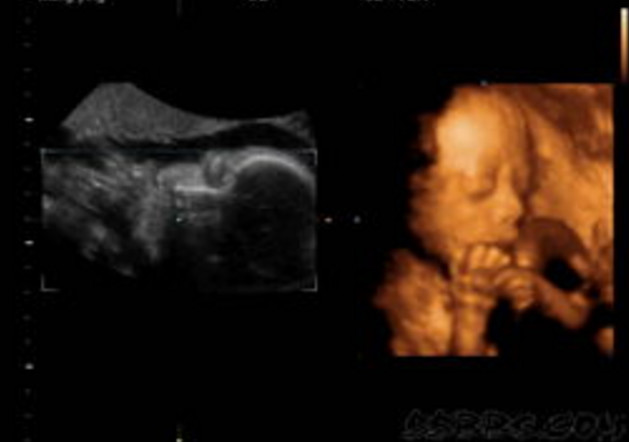

30岁的小孙就有唇裂,修补过的疤痕仍很分明。在最近一次三维B超显示,腹中的胎儿居然中度唇裂。她通知大夫,由于她诞生就有唇裂,小时老是被讪笑和厌弃。所有,无论怎样也要流掉腹中的宝宝,她不想让她的孩子再经历这样的经历。

大夫却通知小孙,现在已经孕21周,如果引产对身材损伤十分大,如果在次怀孕,不能包证就不会得唇腭裂,第二次仍会怀上唇腭裂宝宝的几率约为4%,假如怀过两次唇腭裂的宝宝,第三次怀上唇腭裂宝宝的几率会提升到14%。如今婴儿唇腭裂整形手艺,已经十分胜利,即使是重度的唇腭裂,仍是能够修补得简直看不出来了。倡议把孩子生上去,不要由于这点瑕疵,就将宝宝的性命闭幕。